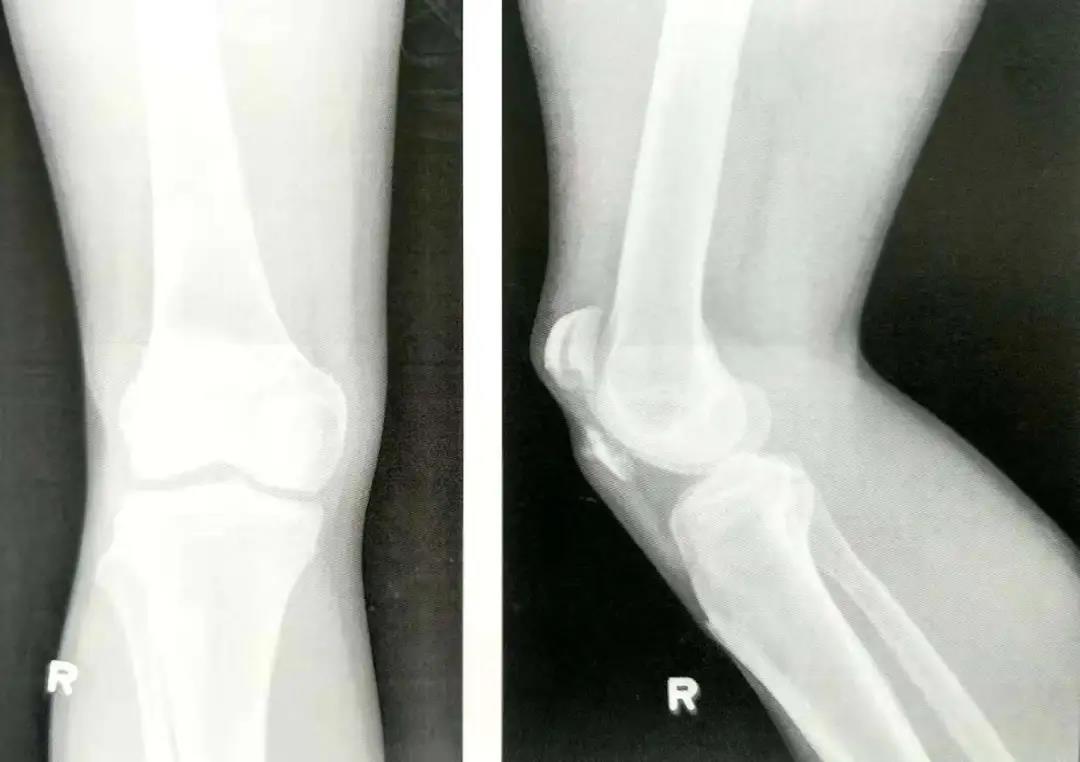

髌骨骨折手术技巧!

- 外科手术的目的是为了获得解剖复位,并在骨折愈合前以内固定的方式来维持复位状态,恢复髌骨骨折后的伸肌装置。

- 在穿过骨折线之前,可用术中透视(正位和侧位)直视下或将手指伸到髌骨下触摸的方式来确保骨折已复位。

- 在直视,触摸或同时借助于术中透视的方式下确保髌骨的关节面达到充分复位,这点非常重要。

- 在关闭伤口前用术中透视或X线评估骨折复位和内置物的位置情况。